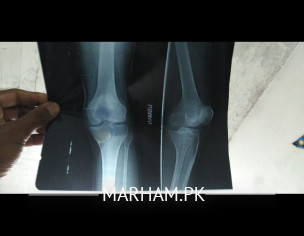

I have too much pain in my knee. ghr jaty huy Bick ny hit kiyh jis sy waja sy knee mur kr sedha ho gya tha lkin ten days sy Dard khtm ni ho re Dr ny one week ki medicine di ha or aj x ray kiyh ha kindly check my x ray and guide me what to do I .

looks like fracture..kindly do CT to confirm...if no fracture then can do MRI later to look for meniscus or ligamentous injury

You should see orthopedic Surgeon near you for proper examination of your knee . With knee injury there are chances of ligaments damage or other structures inside and outside the knee. May need MRI knee depends upon the findings of examination by Orthopedic Surgeon.

you need to do an MRI and consult an orthopeadist